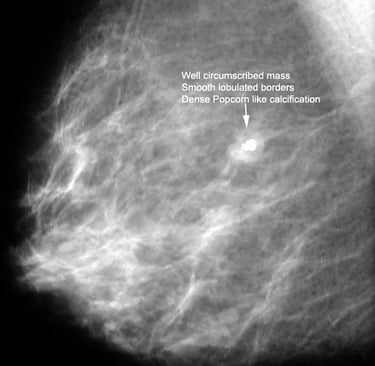

Mamografi (Altın Standart):

Mikrokalsifikasyonlar: LR (+) 15.0. (Özellikle pleomorfik/dallanan tipteyse)

Spiküle Kitle: LR (+) > 20.0.

Luminal A Dominansı: Spiküle (kenarları ışınsal uzantılı) kitlelerin %71'i Luminal A alt tipi olarak sınıflandırılmıştır.

Olasılık Oranı (Odds Ratio): Luminal A alt tipindeki kitlelerin, diğer alt tiplere oranla mamografide spiküle görünüm sergileme olasılığı 10.3 kat daha fazladır (p < 0.001).

Biyobelirteç Korelasyonu: Spiküle görünümün en güçlü öngörücüleri Düşük Ki67 indeksi (< %14) ve HER2 negatifliğidir. Hormon reseptör (ER/PR) pozitifliği de ilişkili bulunmuştur ancak etkisi Ki67 ve HER2 kadar baskın değildir.

Mamografide görülen spiküle kitle, invaziv meme kanserinin Luminal A alt tipi için güçlü bir radyolojik belirteçtir. Bu korelasyonun temelinde tümörün düşük proliferatif aktivitesi (Ki67) ve HER2 gen ekspresyonunun olmaması yatar. Bu veriler, "spiküle kitle" verisinin, biyopsi öncesi Luminal A olasılığını (prior probability) belirgin şekilde yükselttiğini kanıtlamaktadır.